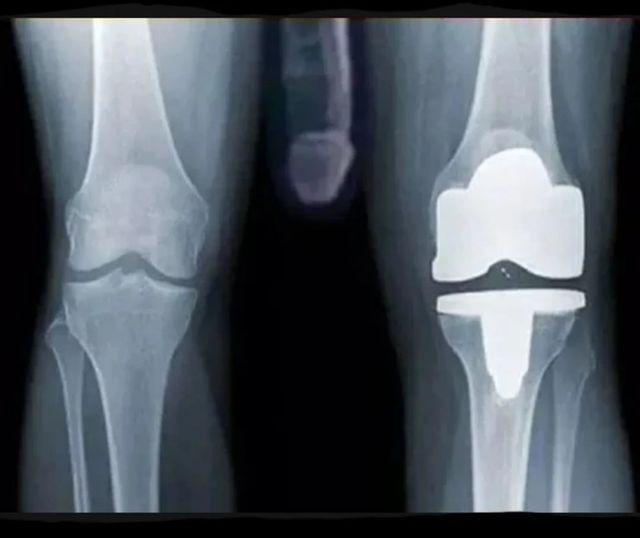

무릎 인공관절 수술한거 엑스레이 보고 가라??!

이제 좀 편하게 살겠네